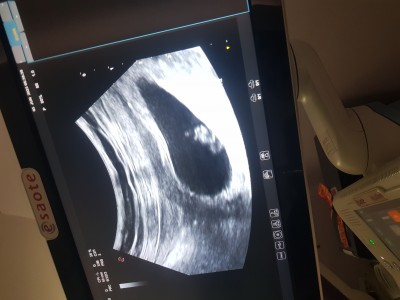

imageplasentanın konumu nerde ise ona gore cinsiyet tahmini yapılıyormuş ben pek anlamadim anlayan varsa bu teorilerden yazabilir mi acaba . Tatlı bir merak her şeyden önce Rabbim sağlık versin tüm hamilelere ve bebislerimize :)

Gebelik haftası 7